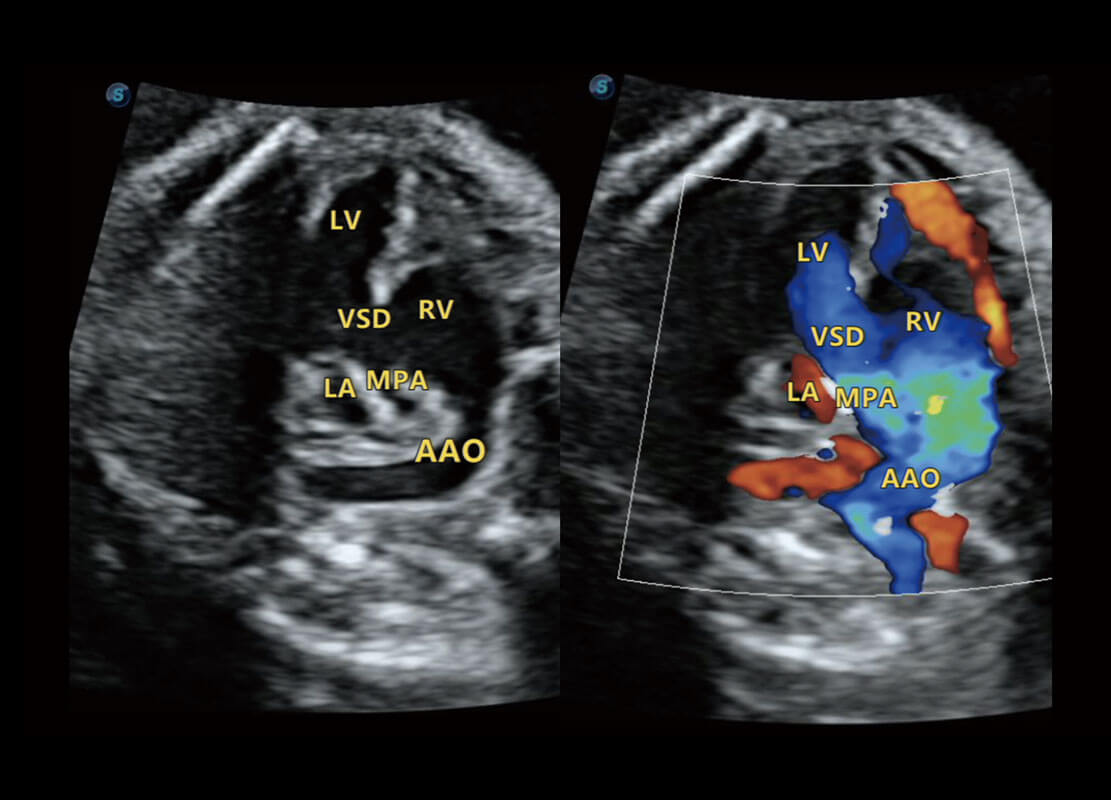

胎心筛查

P60搭载一系列胎儿心脏成像技术,实现精细的胎儿心脏评估。

• 四腔切面

• 四腔心血流

• 右室双出口